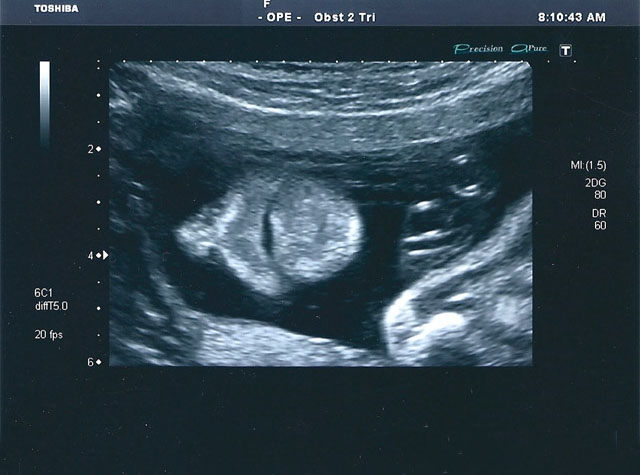

inicialexames a clinicapreçáriogaleriaFAQcontactos